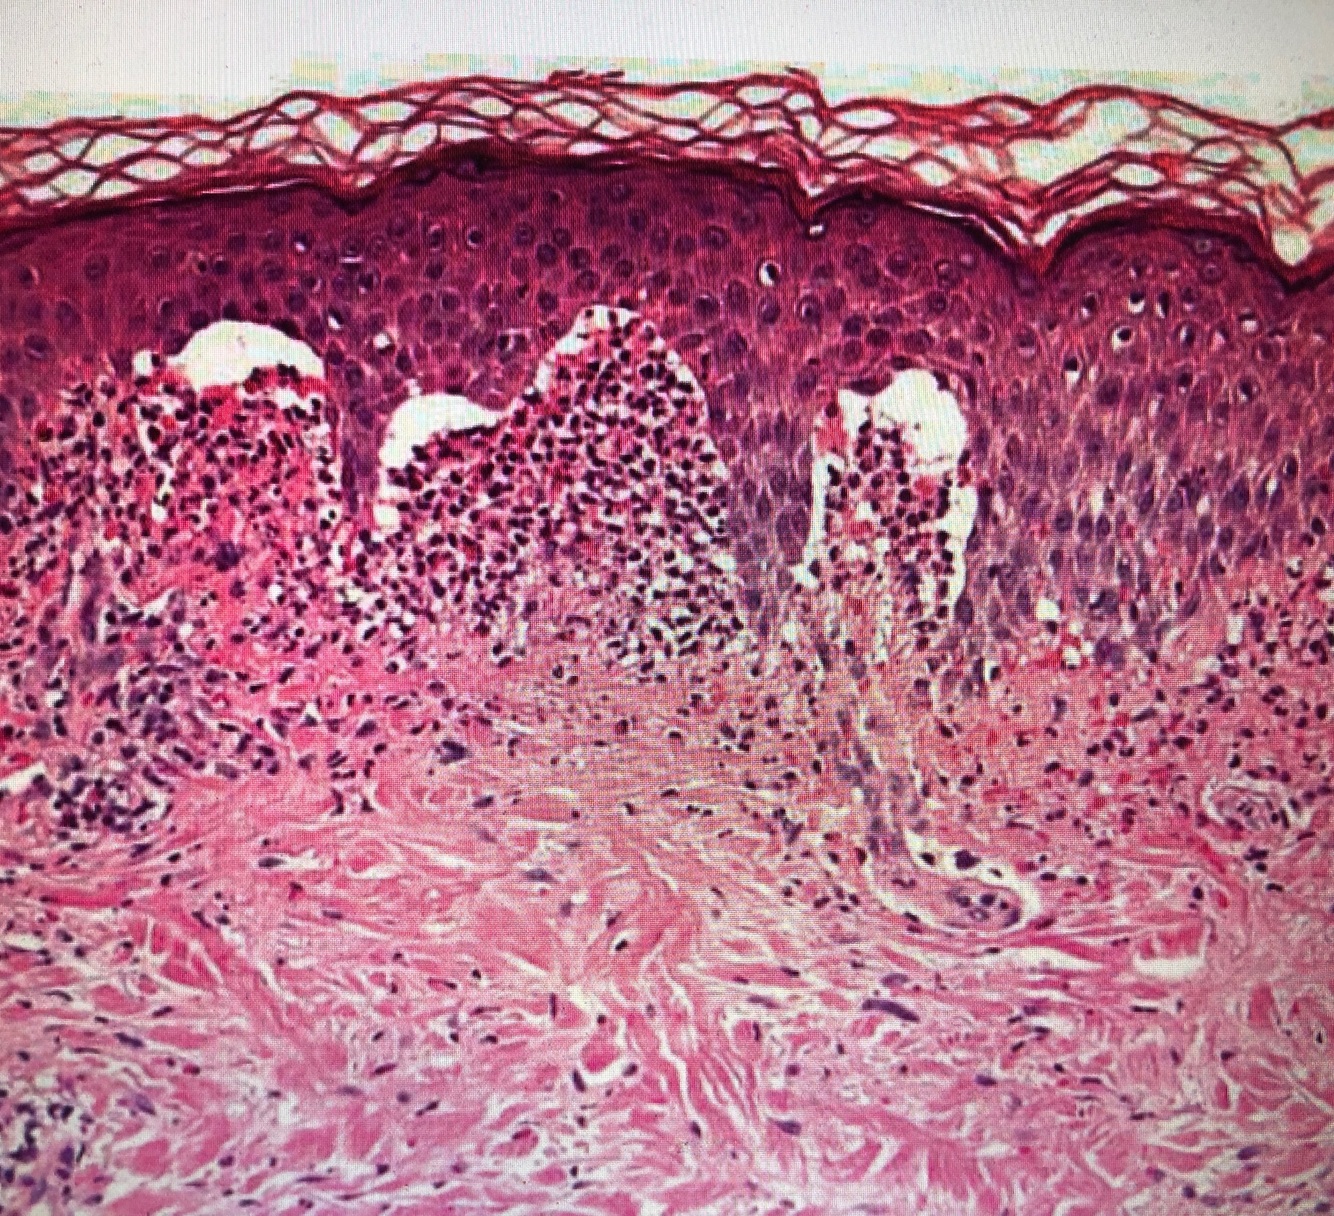

Qual diagnostico?

PF (acantolise, clivagem epidermica alta)